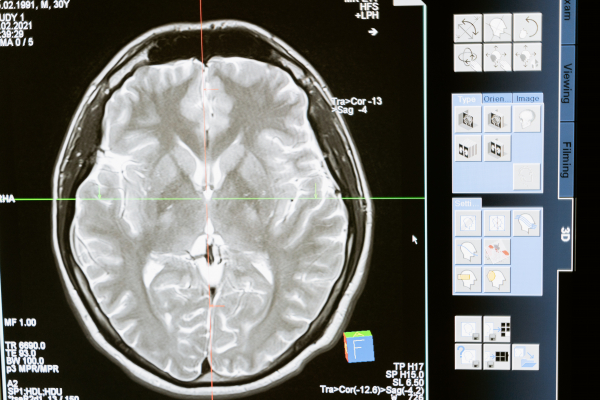

Μια απλή τομογραφία εγκεφάλου μπορεί να διαγνώσει τη νόσο του Αλτσχάιμερ γρήγορα και με ακρίβεια

Ένας νέος αλγόριθμος μηχανικής μάθησης μπορεί να διαγνώσει τη νόσο του Αλτσχάιμερ από μία μόνο μαγνητική τομογραφία εγκεφάλου, χρησιμοποιώντας ένα τυπικό μαγνητικό τομογράφο που υπάρχει στα περισσότερα νοσοκομεία.